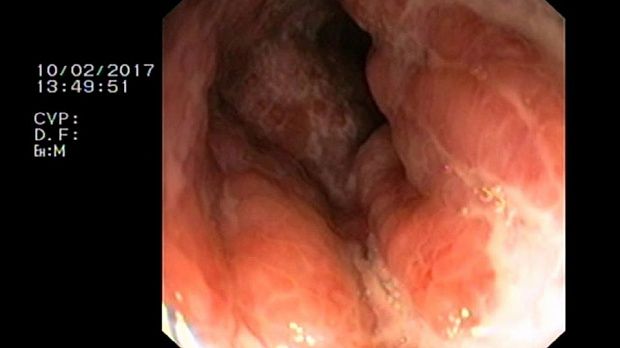

- Атлас